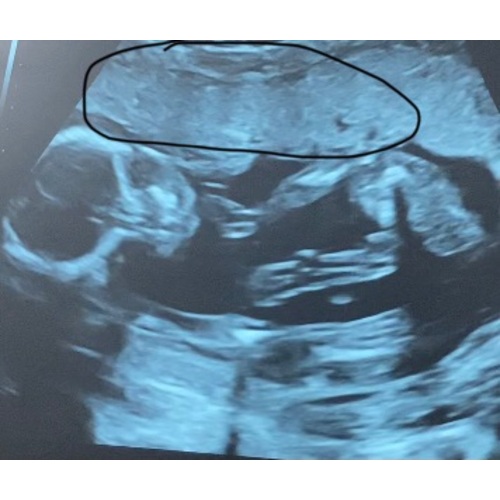

Op de echo foto kijk je tegen het gezicht van de baby aan en ligt ze dus met de zijkant tegen de placenta aan. Bij 19 weken kan dat echter snel veranderen, dat ze gisteren zo lag wil niet zeggen dat het vandaag nog steeds zo is. Als je vragen of zorgen hebt over het voelen van je kindje dan zou ik dit bespreken met je gynaecoloog.